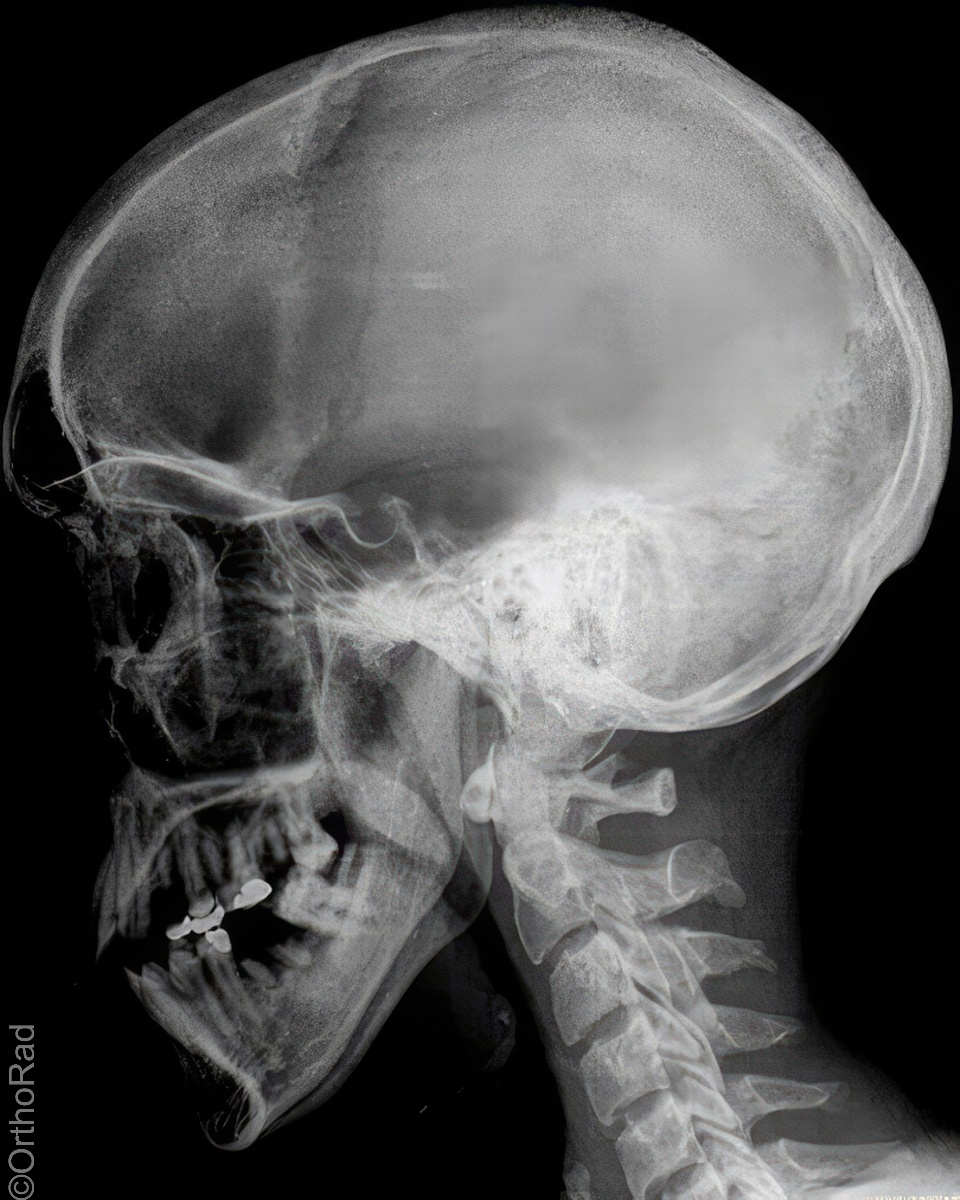

Schädel lateral

Indikation

Fremdkörper-Lokalisation vor MRT, Shuntventil-Kontrolle

Lagerung

Schräg-Bauchlage mit aufstützender Hand der anliegenden Schädelseite

Beine leicht angezogen

Kopf streng seitlich

Medianebene parallel zum Tisch

Kinn und Stirn auf einer gedachten Linie (D.-H. nicht relevant)

Qualitätskriterien

Vollständige Darstellung des gesamten Schädels, weitgehend deckend der Konturen, vordere und hintere Schädelgrube, Orbita, Kieferhöhlen und Jochbein. Zudem deckungsgleich von kleiner Keilbeinflügel und äußerer Gehörgang. Strichförmige Abbildung der Sella turcica.